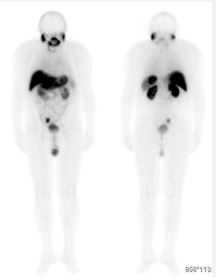

Patient JLN, male, 79 years old, initial serum PSA 9.4, was diagnosed in 2010 with prostate Gleason 7 (3 + 4). He underwent a radical prostatectomy with standard lymphadenectomy still in 2010. Results of the pathological anatomy of the surgical specimen showed: Gleason 7 (4+3), free margins, T2cN0M0, no lymph nodes involved. It evolves uneventfully until in 2014 a biochemical recurrence was diagnosed and was then submitted to salvage radiotherapy (7000GY, 35 sections), with a nadir of 0.25 in May 2015. After 2 years of radiotherapy, he returned to have a new elevation of PSA, and in 2019 it had a PSA doubling time less than 6 months. He was restaged with a PET-PSMA (Figure 1), which showed pelvic lymph node enlargement in the right external iliac chain, measuring 2.5 cm in the longest axes, coexisting another lymph node of 0.5 cm immediately below the bifurcation of the ipsilateral common iliac artery, without other distant injuries. As the patient in question had good clinical status and had no evidence of other metastases, we opted for inclusion in the experimental protocol of radioguided pelvic lymphadenectomy with PSMA - 99mTc.